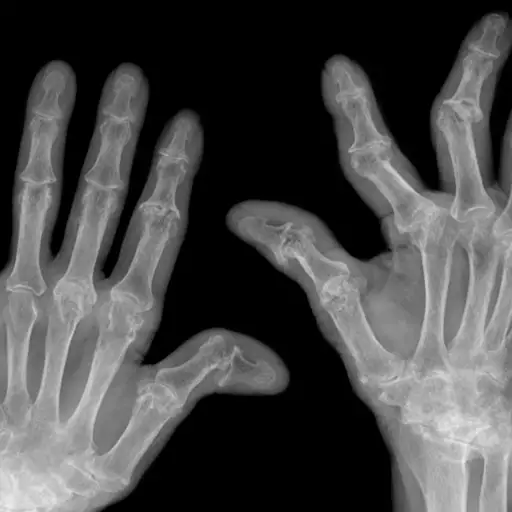

手部x光显示类风湿关节炎晚期

iStock

依赖成像测试

你的风湿病医生可以通过在诊断时获得基线图像,然后根据需要定期进行新的扫描来更好地了解风湿性关节炎是如何影响你的关节的。“你可以期待你的手,手腕和脚的x光,”Batt医生说。“如果你的关节肿了,我们可以轻拍这个部位来测试液体。”一些医生会安排更敏感的成像测试,比如CT扫描、超声波或核磁共振成像,但这并不常见。“只有少数病人需要核磁共振成像,”Ludmer博士说。